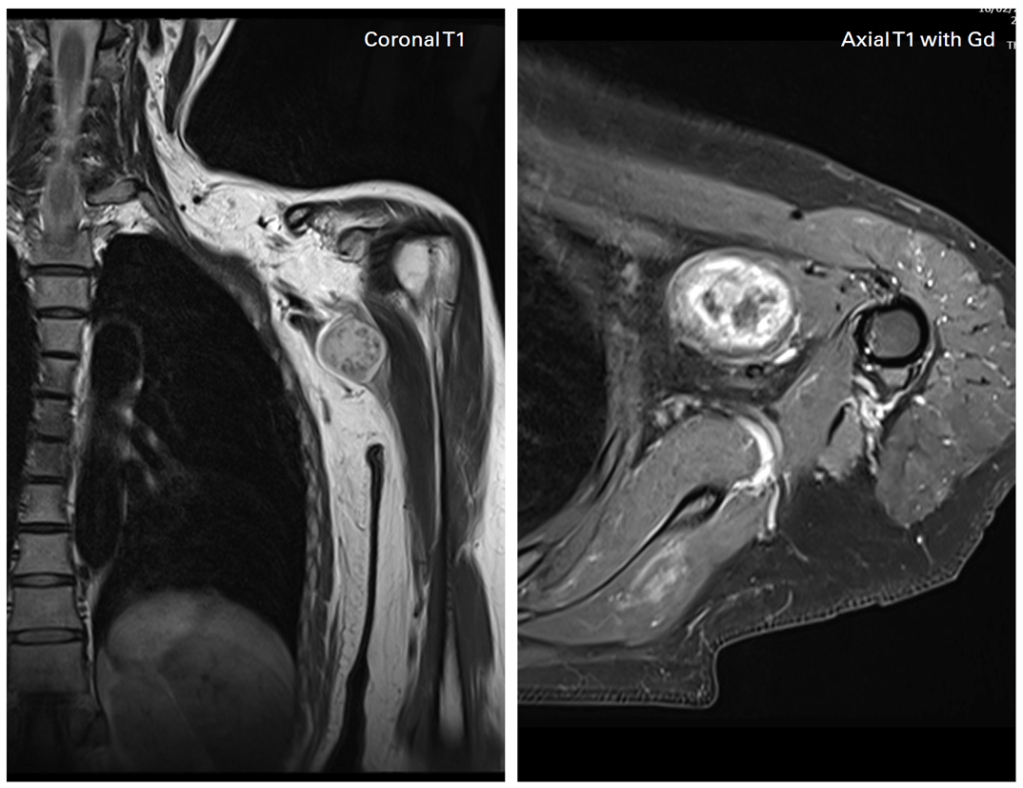

Dedicated imaging of the brachial plexus revealed a nerve sheath tumor affecting the plexus.

The patient’s prolonged pain, along with autonomic changes, was consistent with secondary Complex Regional Pain Syndrome (CRPS) triggered by the underlying nerve pathology.